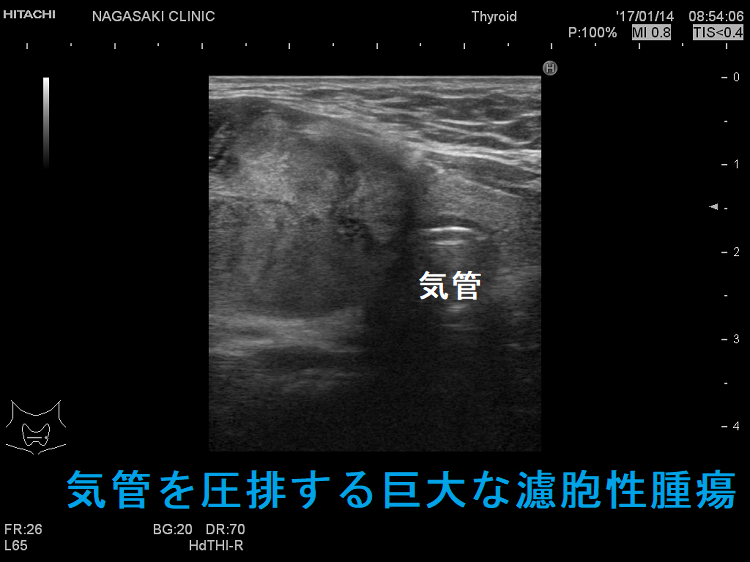

微小浸潤型濾胞癌でも巨大なものは、血管浸潤・遠隔転移します。写真のケースは 4cm以上の微小浸潤型濾胞癌で、切除標本にて血管浸潤を4カ所以上認め、Ki-67 labeling index 7% 高値(>5%)だった(エコーでは内部血流が少なかったのに)。